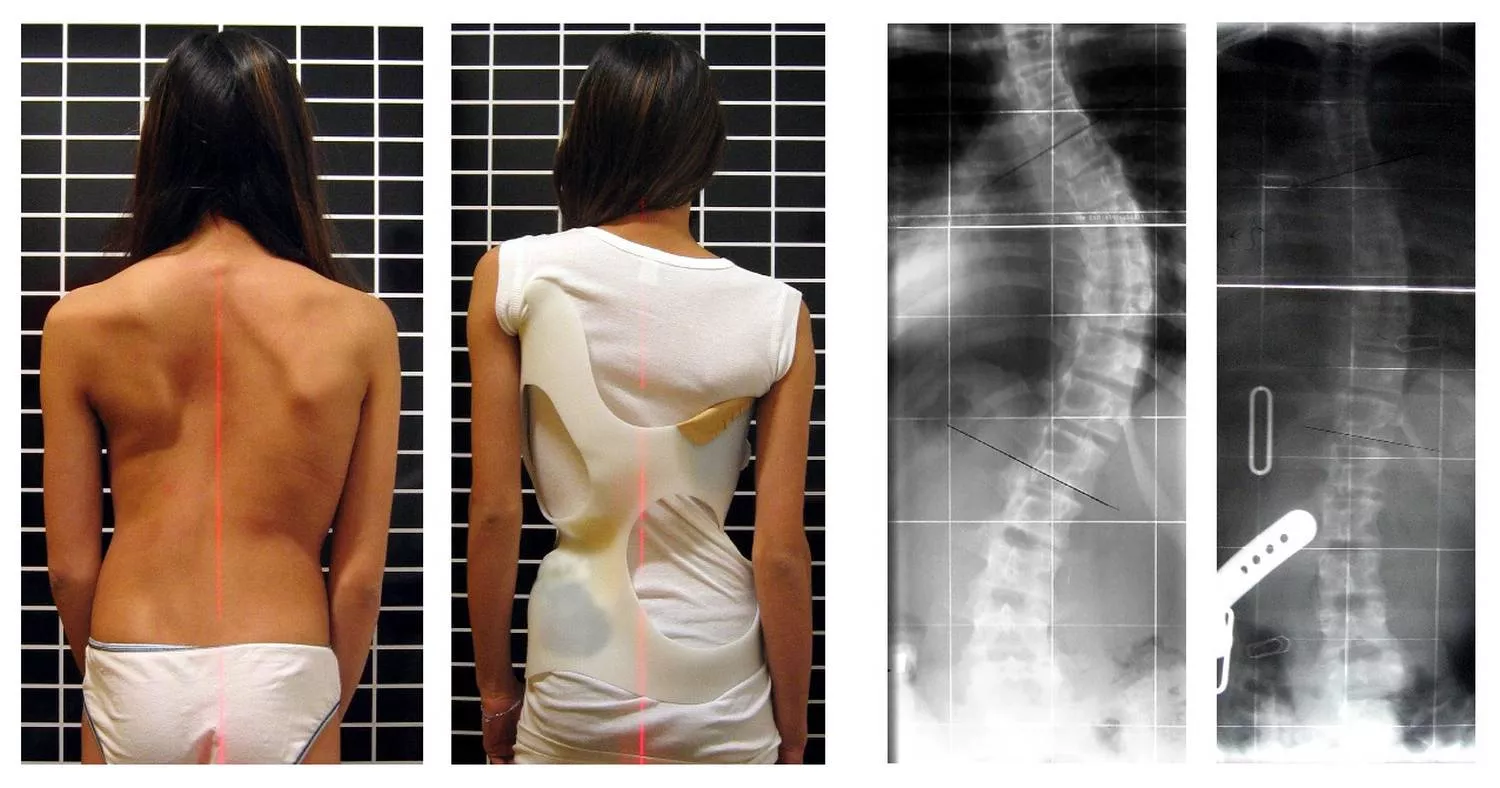

Konzervatív módon, korzettel eredményesen kezelt gerincferdülés (szerző: Weiss HR; liszensz: CC BY 2.0, Wikimedia Commons)